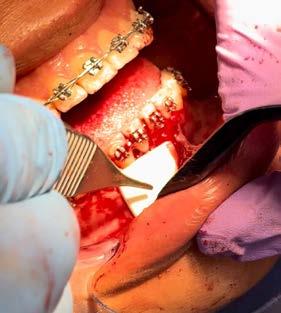

Figura 1. Procedimiento. A) Anestésicos y agujas, B) Toma de presión arterial, C) Preparación de anestésico en carpule y D) Infiltrado de anestésico.

benzocaína tópica ZEYCOMR en la zona del órgano dental a tratar por un minuto, tiempo en el que también se cargó el cartucho del anestésico mepivacaína simple de ZEYCOMR. En jeringa carpule con aguja corta ZEYCOMR se aplicó ligera presión sobre el émbolo del cartucho para verificar la salida del anestésico.

Se infiltraron 2 cartuchos de anestésico con técnica supraperióstica se retrajo el labio en dirección lateral para delimitar el pliegue mucoyugal y mantener la mucosa tensa. Se sostuvo la jeringa anestésica de manera que el bisel de la aguja se dirigiera hacia el diente y se insertó la aguja en la profundidad del pliegue mucoyugal y se

avanzó paralela al diente hasta que entró en contacto con el hueso apuntando hacia el vértice, se aspiró para descartar que la aguja no se hubiera introducido dentro de un vaso. Inyectando alrededor de 0.1 a 0.2 ml de anestésico lentamente por segundo, durante la inyección se utilizó un dedo para aplicar presión externa sobre la mejilla cerca del sitio donde se acumuló la anestesia para evitar el edema local del tejido (Figura 1).